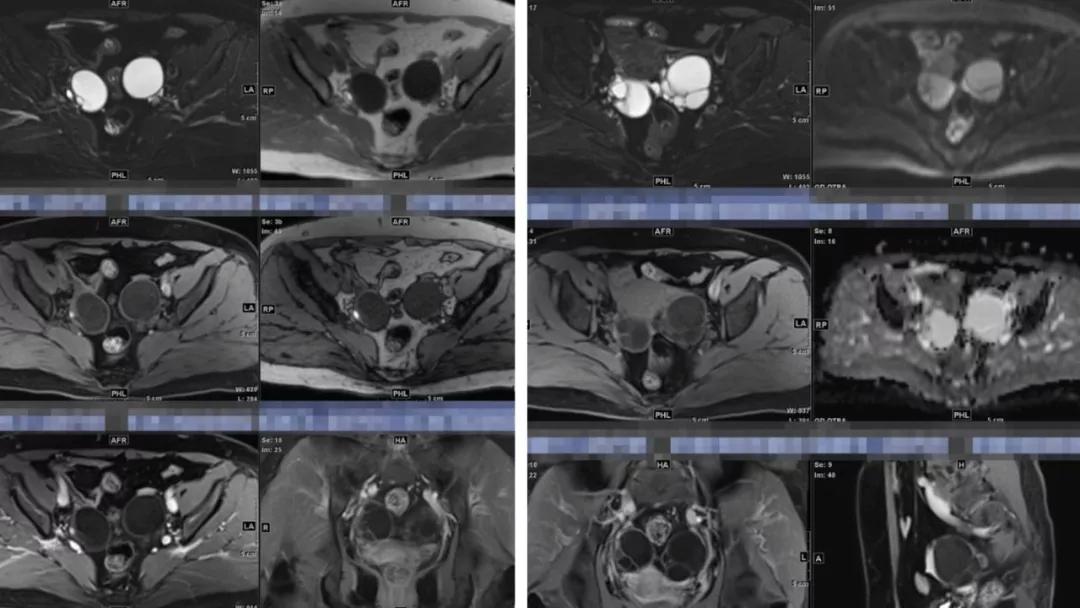

上皮性肿瘤:最常见,恶性多(卵巢癌),良性少。好发于50Y以上,发现时多为中晚期。多呈囊性或以囊性为主的囊实性肿块,完全实性者少见。形态多数不规则,边界模糊,囊壁及房间隔常不规则增厚,菜花样肿物或壁结节,囊实性区域分界不清,实性肿瘤常有不规则低密度或坏死区,可有边界模糊沙粒状或块状钙化,中-高度强化。良性者边界清晰,囊壁薄光整,无壁结节,实性部分呈无或轻度强化。

- 良性及低恶肿瘤强化往往比较轻度,高恶肿瘤强化往往比较快而明显,也就是说,迅速、明显强化的卵巢肿瘤往往代表高度恶性